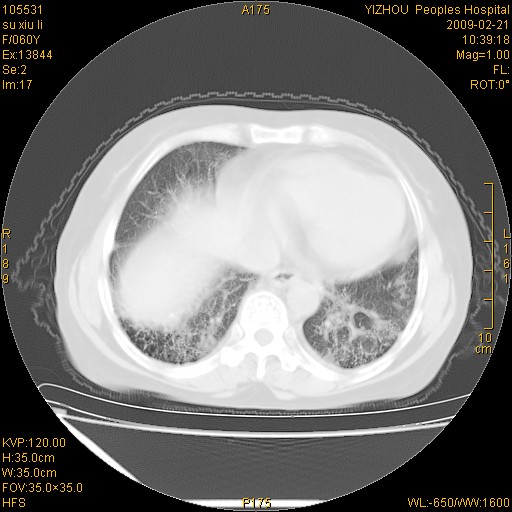

标题: CT18259:两肺间质纤维化? [打印本页]

标题: CT18259:两肺间质纤维化?

女,60岁,反复咳嗽1月。

两肺支扩,以肺为著合并双肺较广范纤维化病变。建议除外结核等病变。

间质性肺炎

符合间质感染,部分纤维化表现

特发性间质纤维化

特发性间质纤维化伴支扩!